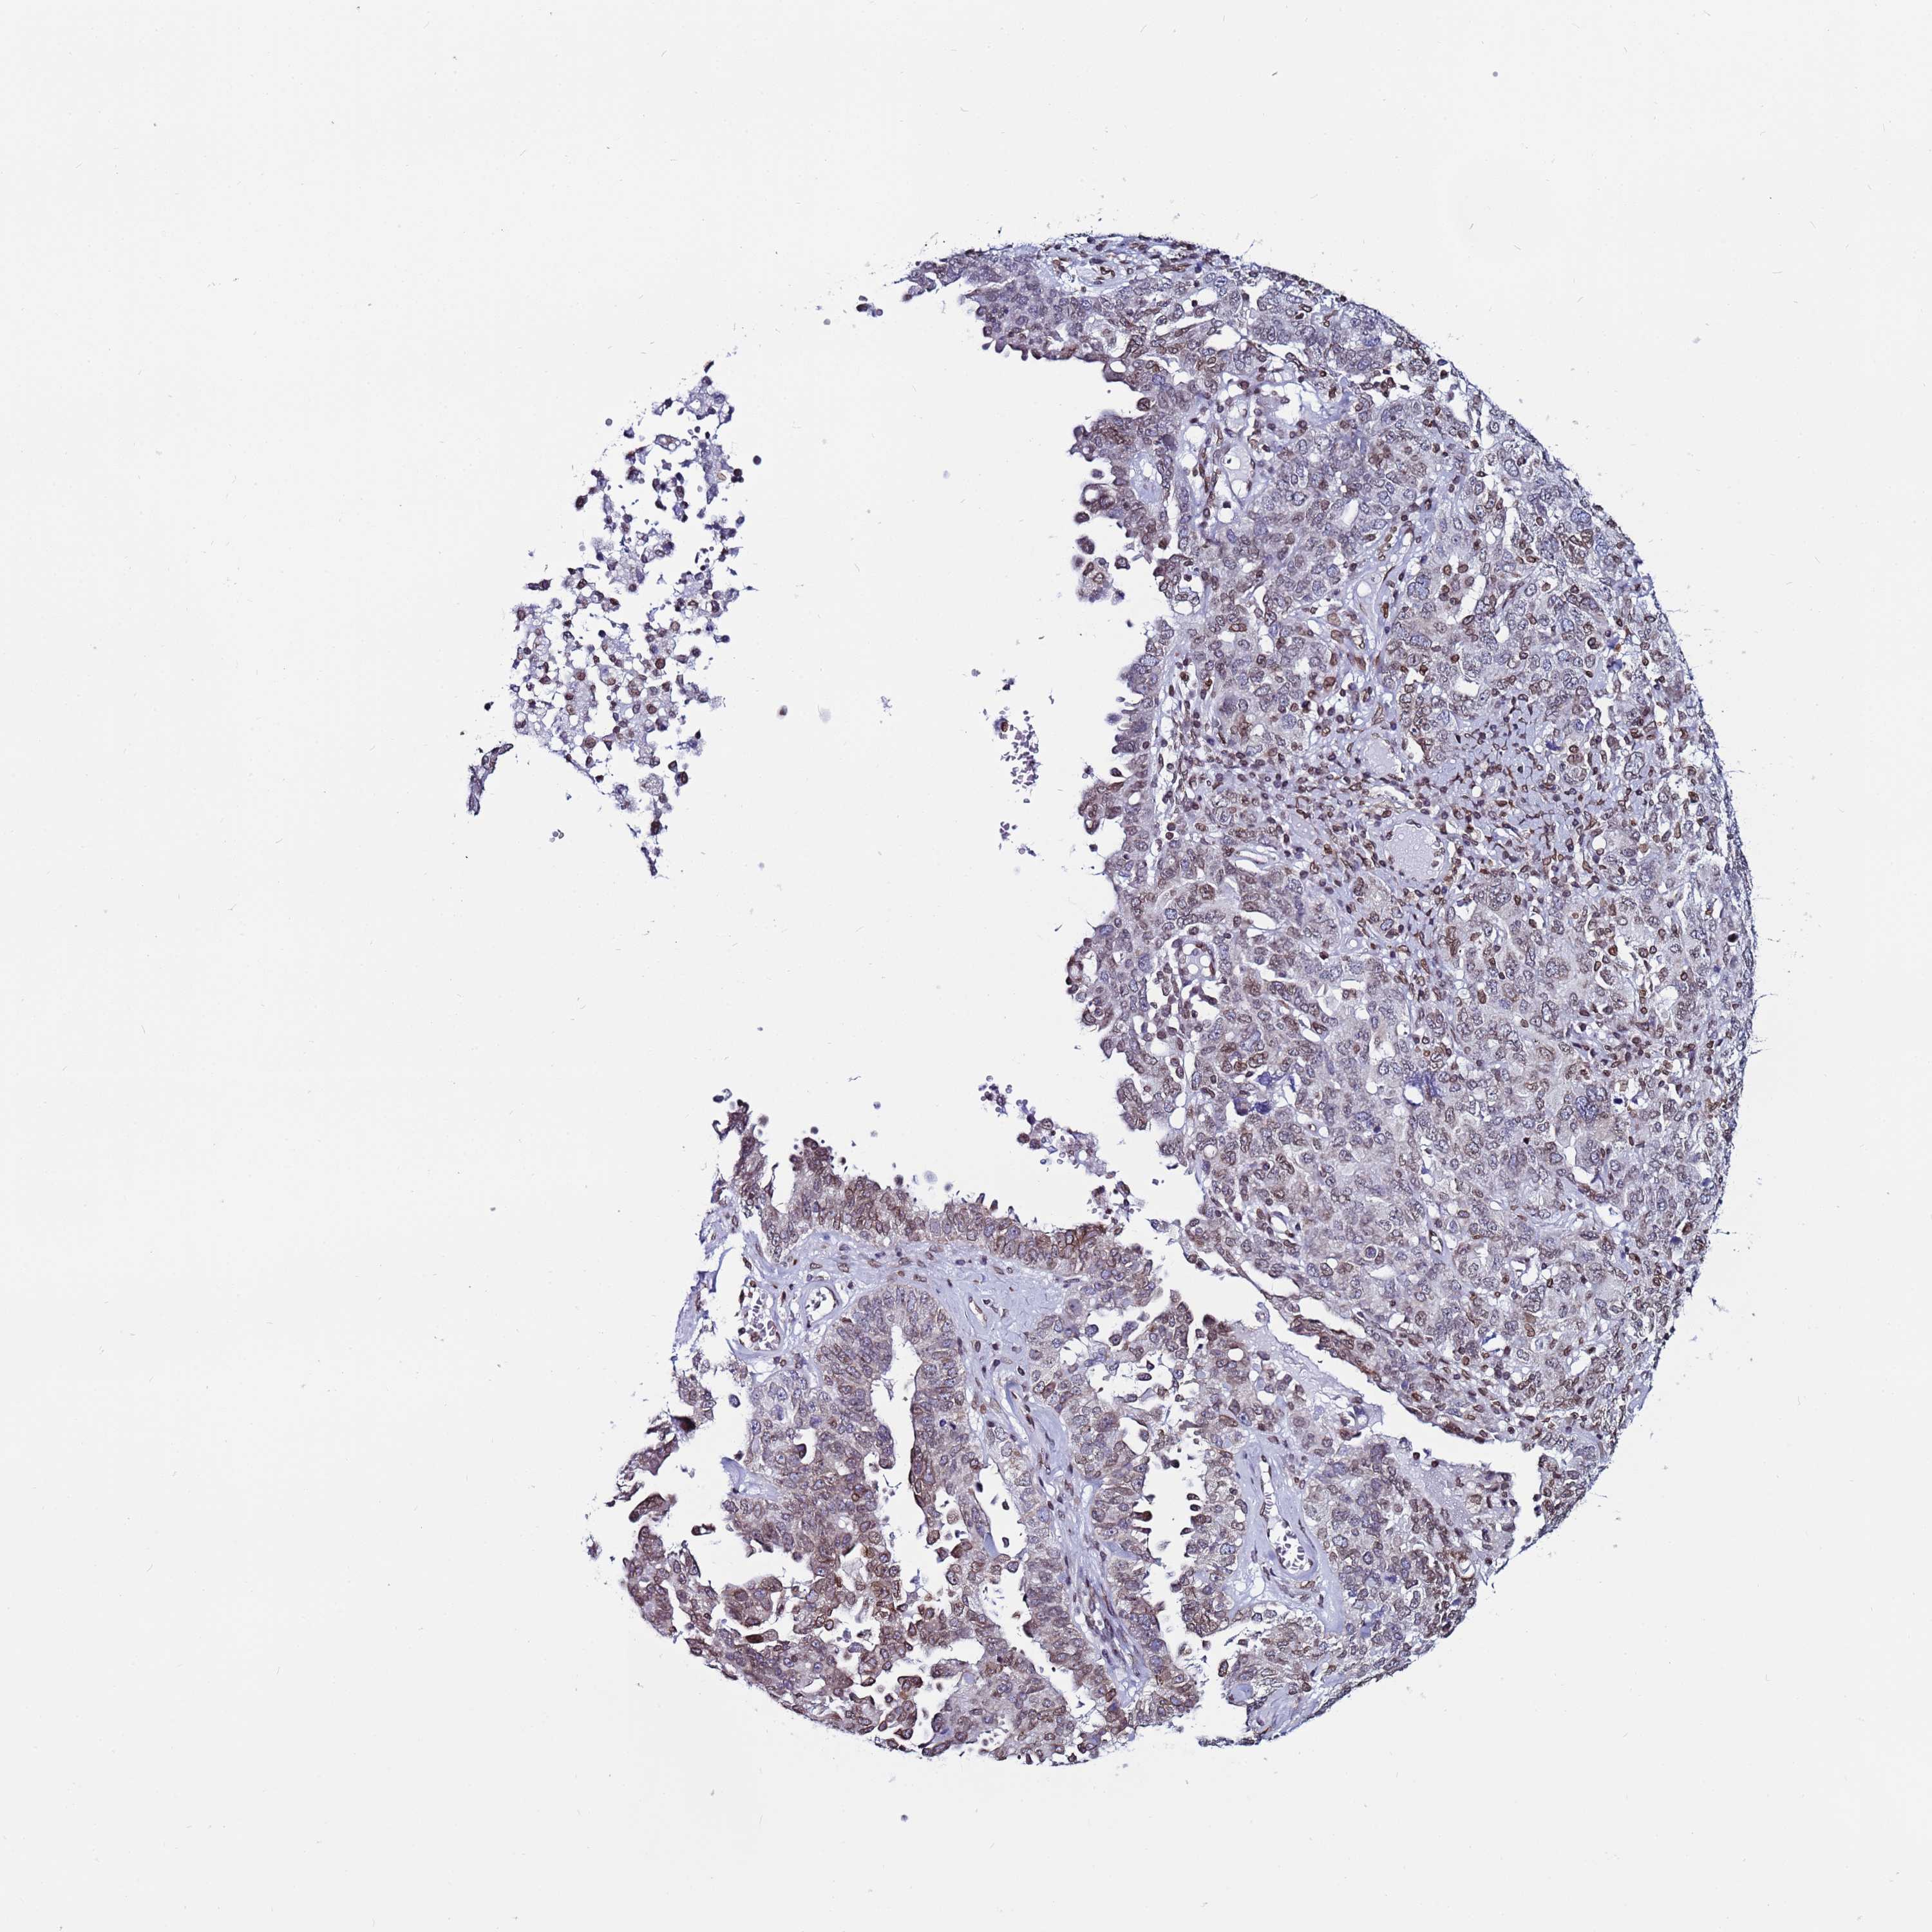

OVARIAN CANCER - Protein expressioni

A mouse-over function shows sample information and annotation data. Click on an image to view it in a full screen mode. Samples can be filtered based on level of antibody staining by selecting one or several of the following categories: high, medium, low and not detected. The assay and annotation is described here.

Note that samples used for immunohistochemistry by the Human Protein Atlas do not correspond to samples in the TCGA dataset.

Antibody stainingi

Antibody staining in the annotated cell types in the current human tissue is reported as not detected, low, medium, or high, based on conventional immunohistochemistry profiling in selected tissues. This score is based on the combination of the staining intensity and fraction of stained cells.

Each image is clickable and will lead to virtual microscopy that enables deeper exploration of all samples and also displays staining intensity scores, fraction scores and subcellular localization as well as patient and tissue information for each sample.

Antibody HPA047151

Cystadenocarcinoma, serous, NOS

Carcinoma, endometroid

Cystadenocarcinoma, mucinous, NOS

Carcinoma, NOS